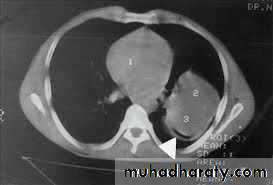

1. CXR 2. CT scan

2) perivesicular pneumocyst or signet ring sign

thoracic surgery